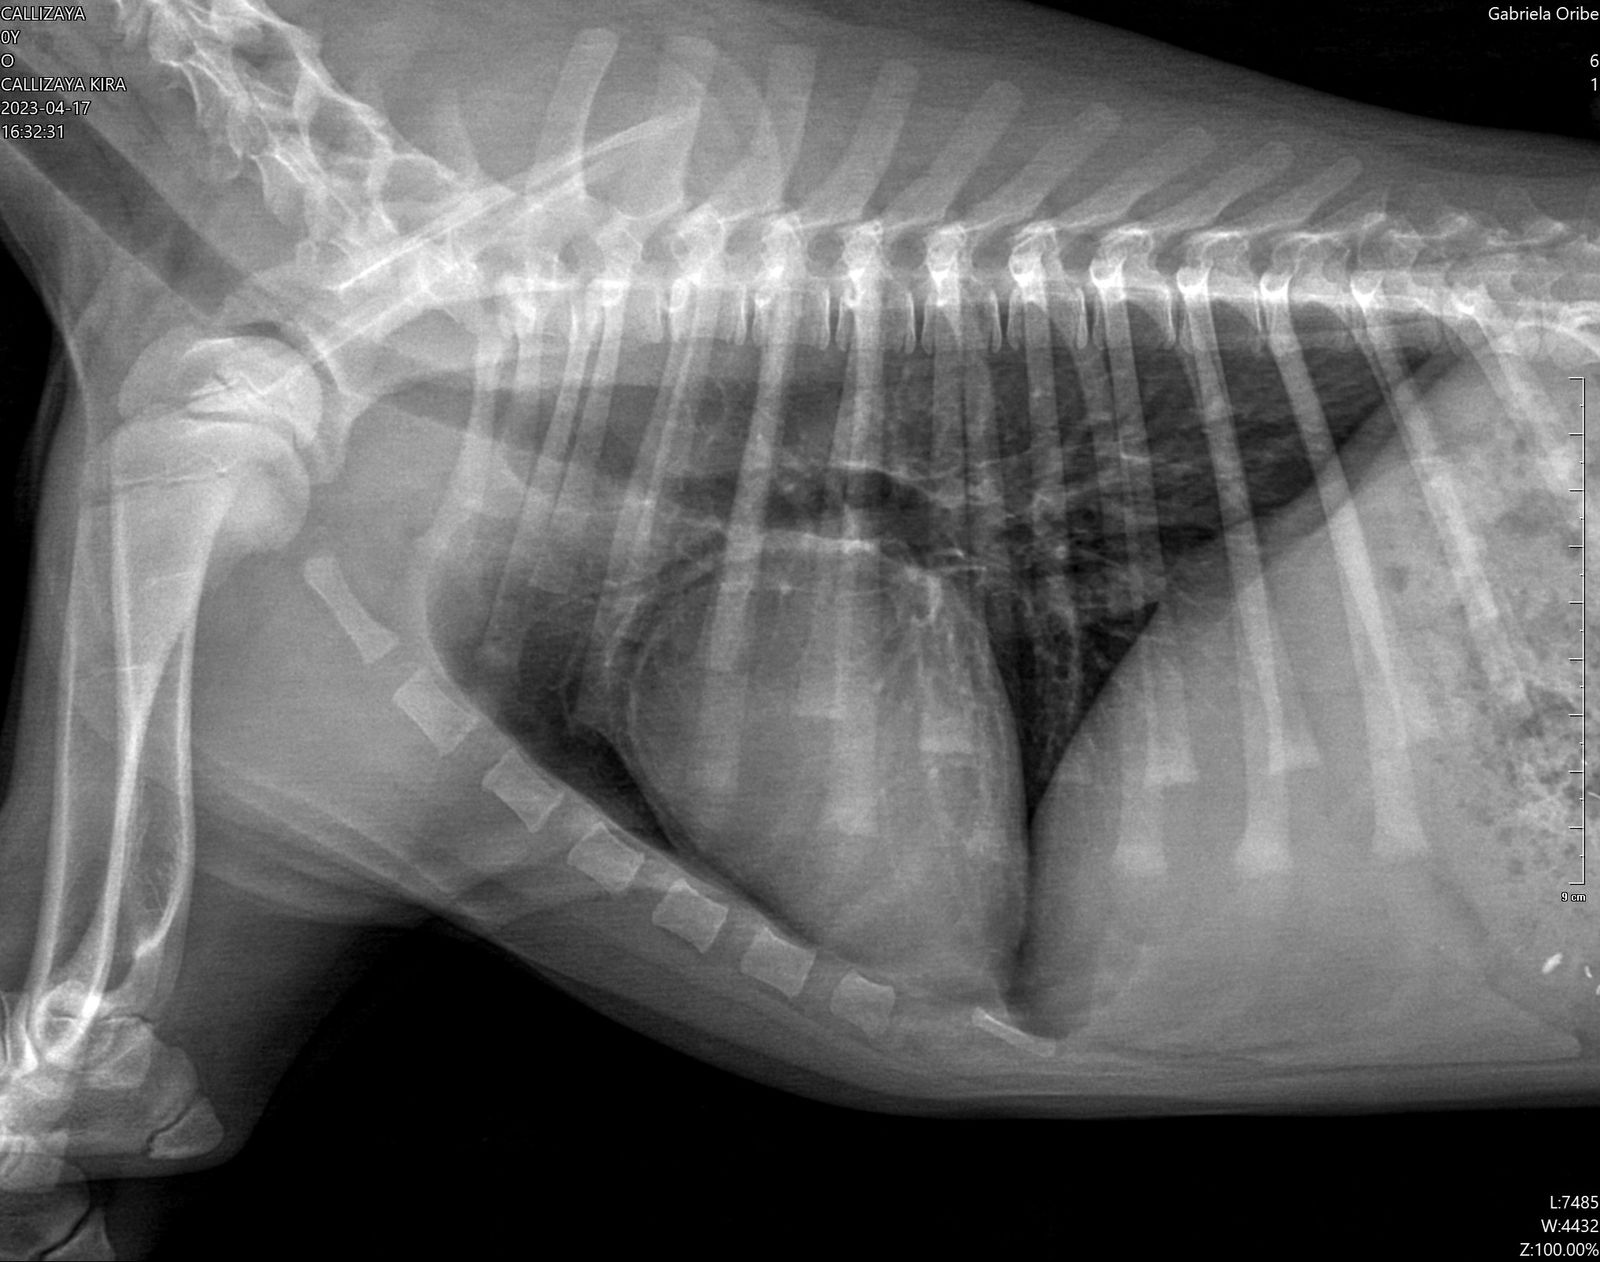

Endoscopía laringo traqueo bronquial por dificultad respiratoria. Se le realizó un RX donde se observa una estrechez en la tráquea